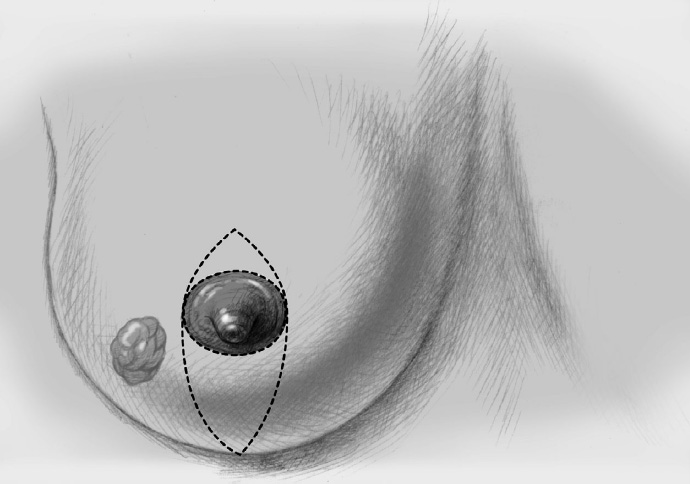

The skin is incised over the tumor region as far as possible (depending on surgeon, tumor size, tumor location, and subsequent treatment). A radial incision may be useful for tumors located in the lower quadrants or directly in the axillary tail of the breast. If the tumor is just beneath the skin, an island of skin over the tumor should be resected also. This can be achieved with both an elliptical semicircular incision and a radial incision. Another form is a purely periareolar incision when the tumor is in a relatively central position (see illustrations below).

The basic decision on whether to use a complex oncoplastic technique is made when the skin is marked preoperatively, with the patient standing or sitting upright. Many surgeons successfully combine the B-plasty incision with periareolar de-epithelialization and excision of a straight or curved ellipse of peripheral skin (Chapter 1.3). When marking the periareolar deepithelialization pattern, an eccentric incision may be necessary to adjust the repositioning of the nipple–areola complex to the anticipated volume displacement.

The skin is incised superficially along the preoperative mark, initially with a scalpel. Many surgeons then proceed using electrocautery needle or scissors.

The periareolar skin is de-epithelialized. Here, too, there are various options. A strip of the most superficial skin layer can be excised with dissecting scissors applied flat or with a scalpel. It is important not to leave behind any surface containing squamous epithelium, but on the other hand the dermis and the important vascular layer beneath it must not be injured. The purpose of periareolar de-epithelialization is to recenter the nipple–areola complex and also to tailor excess skin to the new breast shape following extensive tumor resection.